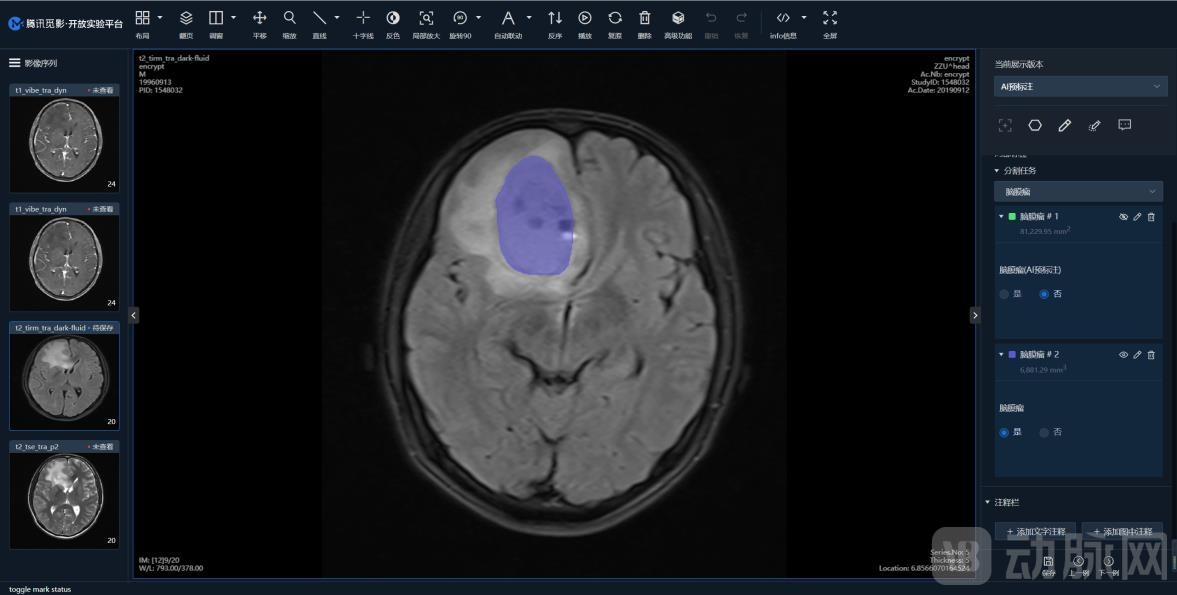

早在2017年,科技部印发《新一代人工智能重大科技项目实施方案》,依托腾讯建设“医疗影像国家新一代人工智能开放创新平台”。目前,“医疗影像国家新一代人工智能开放创新平台”依托腾讯云的技术,已构筑起支持多模态、多病种的SaaS服务平台,支持医疗影像数据的存储、统计、标注、人工智能模型训练、验证等医疗AI研发全流程功能。平台可标注包括眼底病变眼底照片、各年龄段磁共振脑影像、脑胶质瘤磁共振图像、肿瘤代谢PET-CT图像、脑膜瘤磁共振图像、宫颈癌磁共振图像、前列腺癌磁共振图像、甲状腺癌病例图像、食管癌病理图像、宫颈癌阴道镜图像等10种疾病医学影像。平台通过云端开放医学影像AI的共性技术,实现了“有网即用”的高效使用方式,已累计为超过4000个科研单位和用户提供服务,标注医学影像数据超过 7万例。

通过平台可标注脑膜瘤磁共振图像等10种疾病医学影像

腾讯也开放了6个自研的医学影像 AI 模型,助力“医疗影像国家新一代人工智能开放创新平台”能力建设。包括脑出血原因模型、肺结节检测模型、肝脏肝癌分割模型、脑胶质瘤分割模型、眼底多结构分割模型、青光眼样眼底表现分析模型。这些模型涵盖了临床诊断和临床科研等多个应用场景,吸引了更多开发者、医疗机构、科研机构等加入平台。目前平台上已有41个算法模型研究项目集成、应用了上述开放模型。